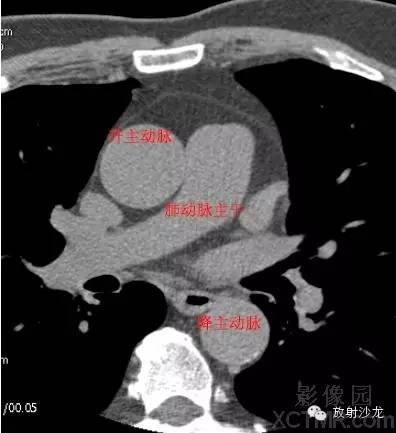

A.Aorta-Ascending Aorta升主动脉

D. Aorta-Descending Aorta降主动脉

PA -Pulmonary Artery肺动脉